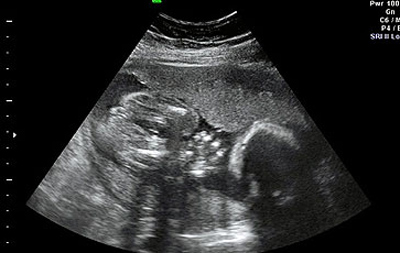

صورة اشعة للطفلة وهي في رحم والدتها